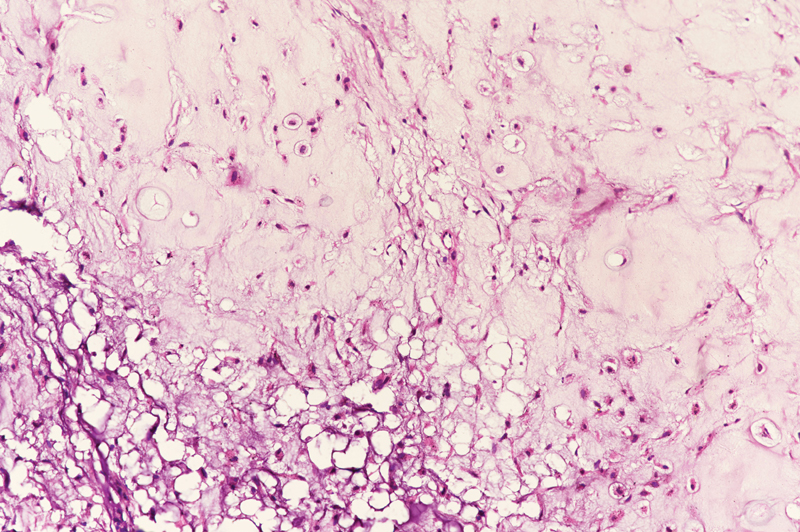

Computed tomography scan of paranasal sinuses ([Fig. 1]) showed large expansile mass arising from the nasal septum filling the entire left and most of the right nasal cavity, measuring 5.5???4.6???3.8?cm and showing multiple calcified areas within the mass suggestive of cartilaginous tumor.

|?Fig. 1? Preoperative computed tomographic image.|

Radiologically, chondrosarcomas are characterized by soft tissue multilobulated expanding mass with areas of nodular and plaque like calcification. On computed tomography, the characteristic findings include presence of chondroid matrix with peripheral and central calcifications, which are scattered. Erosion of the septum and surrounding bony structures is common.[8] On magnetic resonance imaging (MRI), the periphery of the tumor shows contrast enhancement, while the central core that is chondromatous does not enhance. Soft tissue details, intracranial and intraorbital extensions are better appreciated on MRI.[1] [8] The typical calcifications in the cartilaginous tumor associated with chondrosarcoma were also seen in our patient as enclosed in the radiology images. 18-fluoro-2-deoxyglucose positron emission tomography (18F-FDG PET) helps in the tumor grading of the cartilaginous tumor and hence predicts the outcomes. In a study by Feldman et al, maximum standardized uptake value cutoff used to distinguish benign and malignant cartilage neoplasms in 26 operated cartilaginous tumors was 2.0. In this study, sensitivity of 18F-FDG PET was 90.9%, specificity was 100%, and accuracy was 96.6%.[9] Knowledge of the radiological findings can help to preoperatively confirm the diagnosis and plan a surgical resection accordingly.